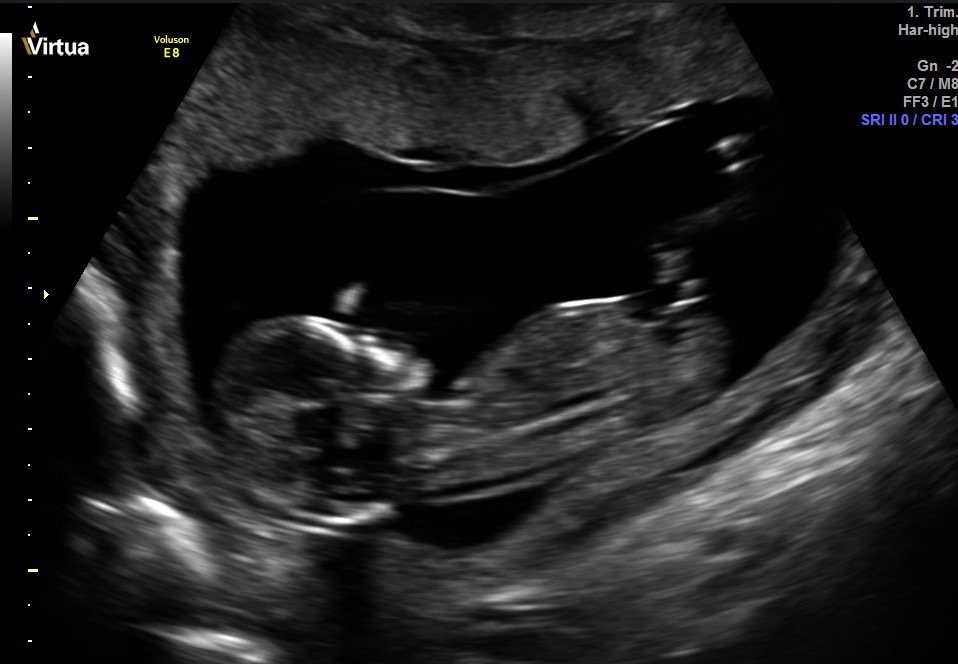

I don't see a nub, but I'm terrible at looking at these things. Can anyone guess the gender? Thank you for your help! I will come back and update on Thursday since we are going for a private scan. Hopefully baby cooperates!Attachment 34055Attachment 34056Attachment 34057Attachment 34061